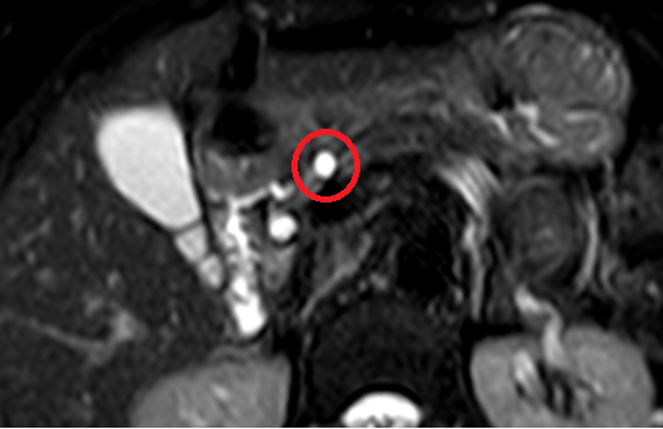

상복부 초음파 상에서 췌장머리쪽으로 8mm크기의 저에코 결절이 보이고 있습니다. 이에 대한 정확한 평가를 위해 추가적으로 췌장 MRI를 시행하였습니다. MRI상 췌장 머리쪽으로 고신호를 가진 8mm크기의 물혹이 관찰됩니다. 이 물혹은 췌관과의 연결성도 보이고 있어, 췌관내유두상점액종양으로 판단되었습니다.

• 췌장MRI: 췌장 머리쪽 8mm 물혹 (빨간 동그라미) 췌장MRI: 췌장 머리쪽 8mm 물혹 (빨간 동그라미)